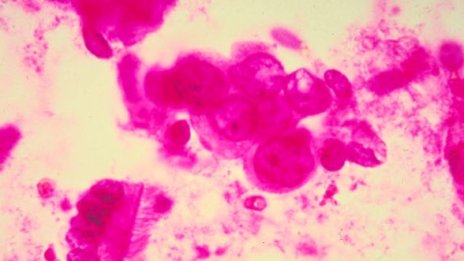

Ракът може да се унищожава с помощта на стволови клетки